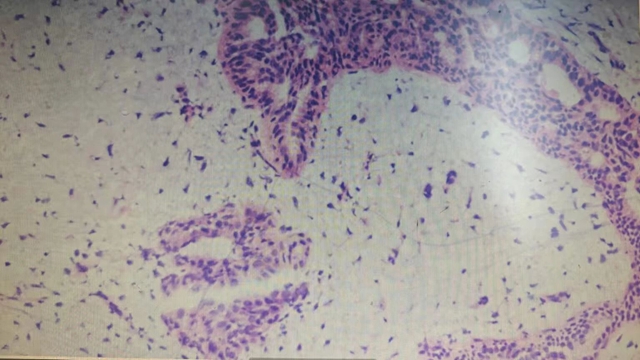

科室冷婕副教授接診后,結(jié)合楊女士帶來(lái)的彩超報(bào)告及查體結(jié)果,高度懷疑為乳腺腫瘤。為了明確性質(zhì),冷婕為楊女士進(jìn)行了空芯針活檢,病檢結(jié)果提示:交界性分葉狀腫瘤。

什么是乳腺分葉狀腫瘤?

乳腺分葉狀腫瘤是一種纖維上皮性乳腺腫瘤,占女性乳腺腫瘤的0.3%-1%,40-50歲女性為高發(fā)人群,男性罕見(jiàn)。

根據(jù)世界衛(wèi)生組織(WHO)標(biāo)準(zhǔn),它可分為三類(lèi):

良性分葉狀腫瘤

交界性分葉狀腫瘤(低度惡性)

惡性分葉狀腫瘤(高度惡性)